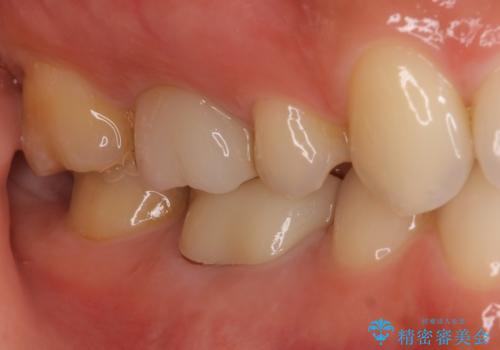

フルジルコニアクラウンを装着してからは、気になっていた金属の縁がなくなり、また、咬み合わせも非常に安定しており、患者様には大変満足していただきました。